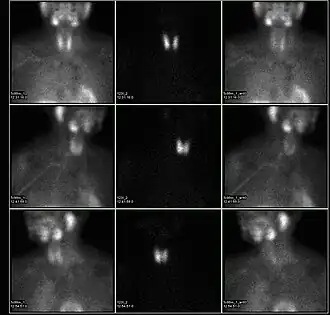

A nuclear medicine parathyroid scan demonstrates a parathyroid adenoma adjacent to the left inferior pole of the thyroid gland. The above study was performed with Technetium-Sestamibi (1st column) and iodine-123 (2nd column) simultaneous imaging and the subtraction technique (3rd column).

A nuclear medicine parathyroid scan demonstrates a parathyroid adenoma adjacent to the left inferior pole of the thyroid gland. The above study was performed with Technetium-Sestamibi (1st column) and iodine-123 (2nd column) simultaneous imaging and the subtraction technique (3rd column). -